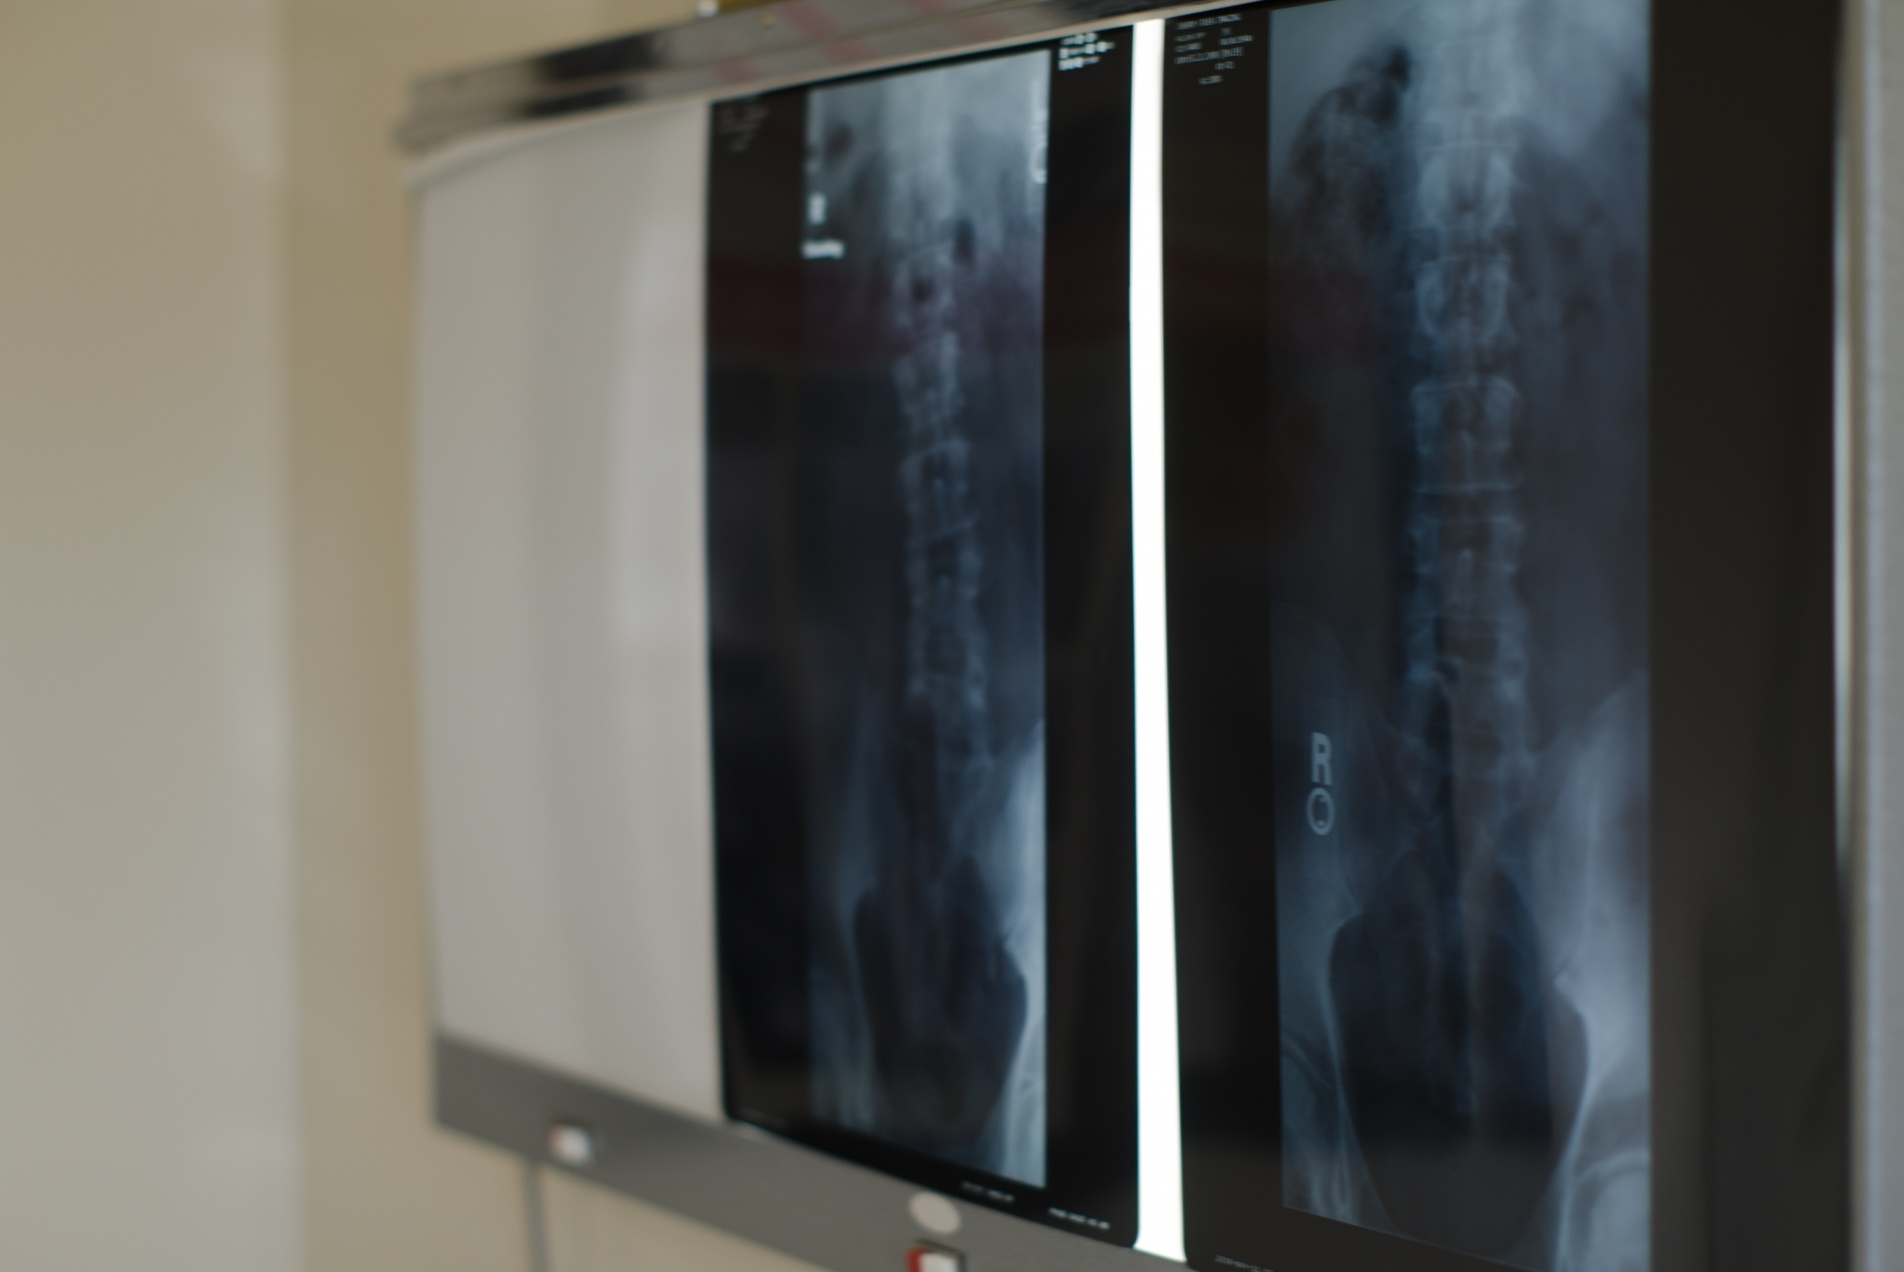

レントゲン画像は、皆さんがどのような環境で生活をしてきたのかを教えてくれます。姿勢のくせやサブラクセーション(神経圧迫)がどれくらい放置されたか知る事ができ、椎骨の捻れや、ゆがみも分かります。